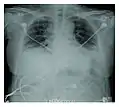

Rapid progression from initial symptoms to respiratory failure is a key feature. An X-ray that shows ARDS is necessary for diagnosis (fluid in the small air sacs (alveoli) in both lungs). In addition, a biopsy of the lung that shows organizing diffuse alveolar damage is required for diagnosis. This type of alveolar damage can be attributed to nonconcentrated and nonlocalized alveoli damage, marked alveolar septal edema with inflammatory cell infiltration, fibroblast proliferation, occasional hyaline membranes, and thickening of the alveolar walls. The septa are lined with atypical, hyperplastic type II pneumocytes, thus leading to the collapse of airspaces. Other diagnostic tests are useful in excluding other similar conditions, but history, X-ray, and biopsy are essential. These other tests may include basic blood work, blood cultures, and bronchoalveolar lavage.

Acute interstitial pneumonia showing a marked reduction in lung capacity_Idiopathic_DAD_3.jpg.webp)